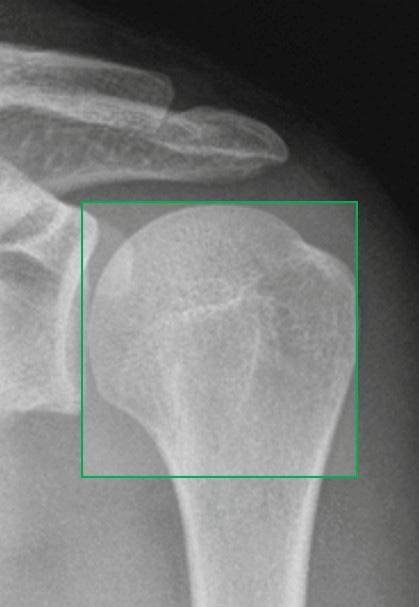

38 SSAS: Behandling av axelfrakturer